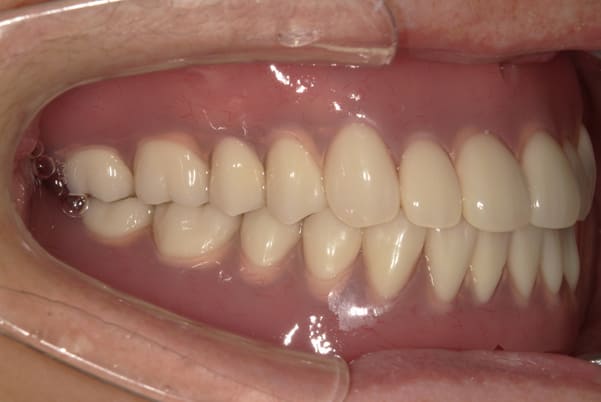

作製した入れ歯は、お食事の際に入れ歯の沈み込みを予防するため、適切なストッパーを付与することで、入れ歯は沈み込まなくなり、お痛みは消失しました。

右下のバネの位置は後ろに、左下のバネは見えづらい形態のバネを用いる設計とすることで笑った際にバネが見えないようになり、気にされることはなくなられました。

裏側の見えない部分は金属を用いることで、お食事の際の入れ歯の動き、沈み込みを抑えお痛みがでづらく、入れ歯の動きが抑制されることで、長期的に残りの歯に負担のかかりにくい設計としました。

こちらは、口を少し開いた時の治療前と治療後の

口元です。

正面から見た時にクラスプが目立たないように、

歯ぐきになじむ素材にて入れ歯を製作し、痛くなく自然に馴染み快適に生活を送れるようになりました。